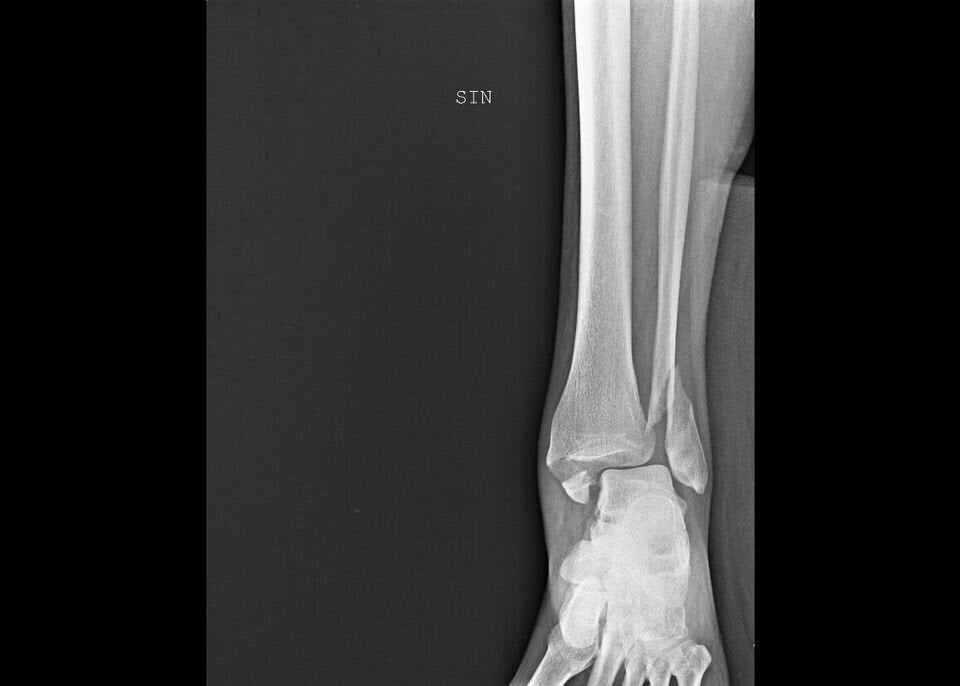

This isn’t the beginning of a novel, but the true story of a woman featured in “Invisibility Is Not A Superpower,” an exhibition that was set up in the atrium of the San Carlo Hospital in Milan, Italy, from Nov. 21 to Dec. 8. Through anonymous photographs and X-rays, the exhibition recounts the tragedy of women arriving at the emergency room and reporting that they have been victims of domestic violence.

“In this exhibition, a voice is given to the bodies and injuries of women who have suffered violence, weaving individual stories into a single narrative,” said photographer Marzia Bianchi. “The lives of the women differ, yet the pattern of violence is repeated, mainly at the hands of a partner, relative or acquaintance.”